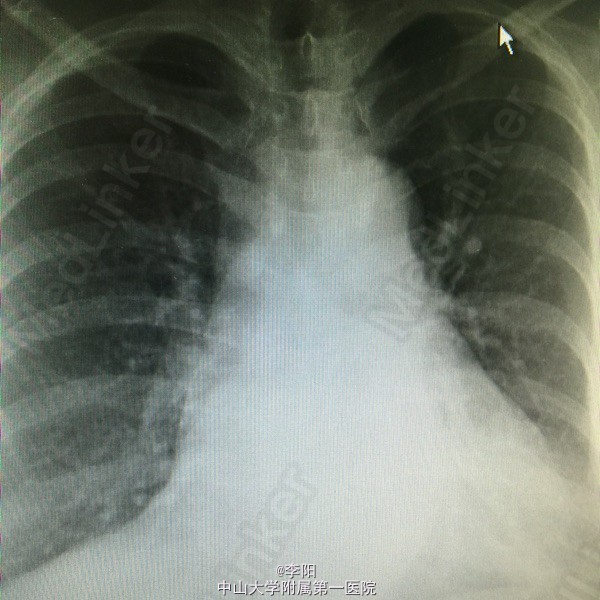

风湿性心脏病一例

风湿性心脏病

该患者一年前出现劳力后气促,走路1000米后可出现,当时无胸闷,胸痛,心悸等症状,伴有双下肢轻度水肿,未予诊治。6月前患者上述症状明显加重,走路200米即可出现气促,伴胸闷,心悸等症状双下肢开始出现重度水肿。